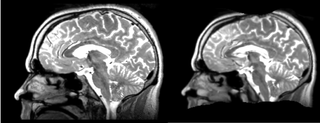

Registration of a t2w image to arbitrary t1 and back via Diffeomorphic Demons Registration module.

current15:08, 21 April 2009Thumbnail for version as of 15:08, 21 April 20091,112 × 426 (295 KB)Rauscha (talk | contribs)Registration of a t2w image to arbitrary t1 and back via Diffeomorphic Demons Registration module.